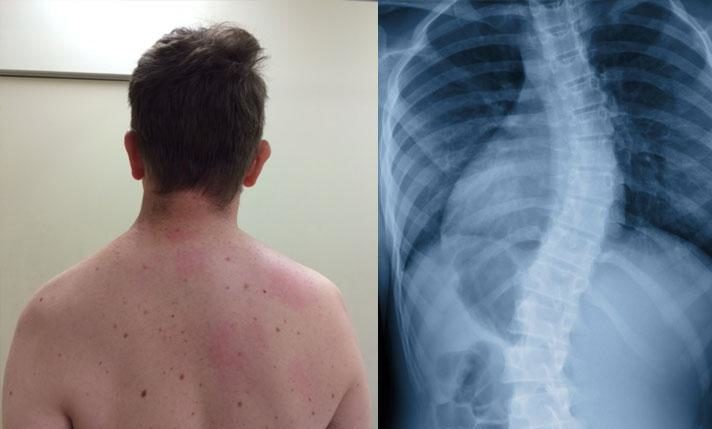

Суть патологии

Сколиоз обычно начинается в детстве или в период полового созревания. Средний возраст пациента – от 10 до 12 лет. В начале патология не вызывает боль. Однако в конечном итоге кривизна приводит к неправильной нагрузке на позвоночник. Перенапряжение мышц и боль являются частыми последствиями расстройства.

Признаки, которые возникают, зависят от того, где деформируется позвоночник. Основываясь на этих двух особенностях, патологию можно разделить на разные типы.

Классификации по анатомии:

- Торакальный: точка искривления располагается в области грудного отдела позвоночника.

- Поясничный: искривление лежит в области поясничной области позвоночника.

- Тораколюмбальный: патология находится в области переходной зоны между грудным и поясничным зонами позвоночника.

- Торакальный и поясничный: точки лежат в пояснично-грудной области позвоночного столба.

В большинстве случаев (85 из 100) врач не может определить причину расстройства. Сколиоз неизвестной причины называется идиопатическим.

- Позвонки растут неравномерно: одна сторона растет медленнее, чем другая.

- В результате одна сторона позвонков занимает больше места, чем другая.

- Вертебральные тела вращаются друг против друга.

- В этом случае позвоночник скорчивается вокруг своей оси и наклоняется вправо или влево.

В дополнение к идиопатическому выделяют и другие формы искривления позвоночника, при которых причину можно выявить. Наиболее распространённые причины:

- врожденные пороки развития;

- нарушенные функции нерва;

- мышечные нарушения;

- системные заболевания;

- износ (если части позвонков изнашиваются в старости, результатом может стать так называемый дегенеративный сколиоз).

Именно поэтому, некоторые заведения достаточно серьезно подходят к отбору будущих студентов. Это уже достаточно серьезное нарушение, которое может стать причиной получения освобождения от службы. Диагностику этого заболевания проводят исключительно при помощи рентгенографии. Серьезным считается заболевание при выявлении таких отклонений: разрушение происходит сразу в 3 и более дисках; сильные, резкие боли при физических нагрузках; хорошо заметная деформация позвоночника.